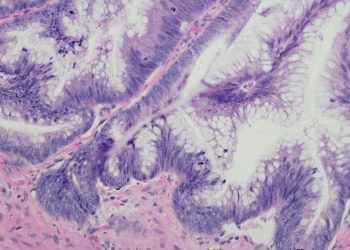

Επιτυχής Ολοκλήρωση της Διημερίδας για τις Γυναικολογικές Νεοπλασίες και Νεοπλασίες Ουροποιητικού και Μαστού

Με μεγάλη επιτυχία ολοκληρώθηκε η Επιστημονική Διημερίδα με τίτλο: «Γυναικολογικές νεοπλασίες και νεοπλασίες ουροποιητικού και μαστού: Θεραπευτικά διλήμματα και νεότερα ...